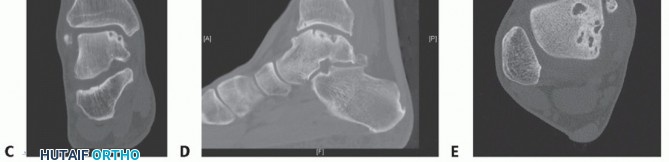

Preoperative weight-bearing radiographs suggest large medial OLT and varus malalignment with some varus talar tilt (TECH FIG 5A,B).

CT demonstrates large-volume medial OLT (TECH FIG 5C-E).

- TECH FIG 5 • A,B. Preoperative radiographs. A. AP and mortise ankle views suggest large medial talar dome OLT and varus alignment. B. Lateral radiograph. C-E. Preoperative CT of largevolume OLT. C. Coronal view. D. Sagittal view. E. Axial view.